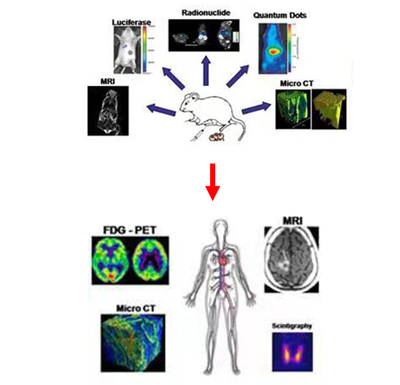

活体动物成像解决方案:

随着对生命科学研究的深入,人们越来越希望能在保持动物正常生理状态稳定的条件下表征细胞或组织的微环境,从而探索细胞组织的功能信息与生命活动之间的关系。通过结合多光子成像、近红外成像及内窥成像等技术,FLIM能够在活体动物中对一定深度的组织进行成像。在通过化学反应发光的生物发光成像(bioluminescence)以及荧光染料(探针)等受激发光的荧光成像(fluorescence)应用中,综合衰减量和穿透能力上的优异表现,近红外I区(NIR-I,700-900 nm)波段, 近红外二区(900~1700nm)荧光探针逐渐被开发,用于探测收集近红外II区波段的InGaAs红外传感器、光学成像镀膜元件工艺日趋成熟,该波段在活体动物组织内低散射、穿透深度大的优势得到发挥,日益成为相关应用领域的关注技术。由于活体成像本身探测的光很微弱,用于自动化、仪器化的活体成像光学系统需考虑以下:

活体动物成像的目的:

基因的表达

观察和追踪靶细胞

优化药物和基因治疗方案

从分子和细胞水平观察药物疗效

同时检测多种分子事件

从动物整体水平上评估疾病发展

对一个动物进行时间、空间、个体发展和治疗影响的多方位追踪